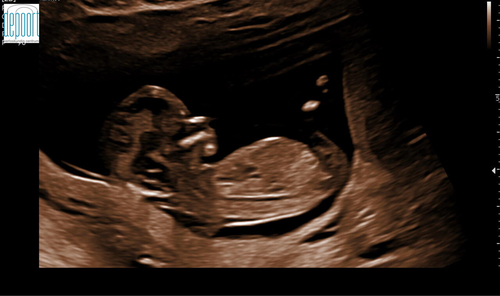

Een jongen! 馃挋 nub wijst flink omhoog.

Op de foto bedoel ik